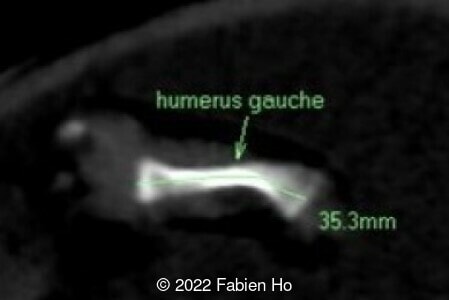

A CT scan was subsequently performed at 32 weeks gestation

The prenatal CT scan showed:

- Very short long bones with curved femurs, tibias and fibulas. The curvature of the long bones reaches a 90° angle concerning for fracture. Upper limbs are moderately curved without fracture.